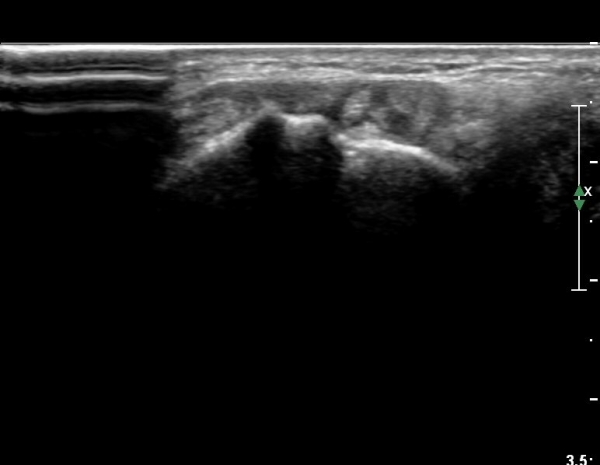

¿ä°ñ Ⱦ´Ü¸é°Ë»ç¿¡¼­ lister's tubercle ̫̿¿¡¼­ ÇÇÁú°ñ ¿¬°á¼º ¼Ò½Ç(loss of cotical continuity)ÀÌ °üÂûµÊ(»çÁø 4).